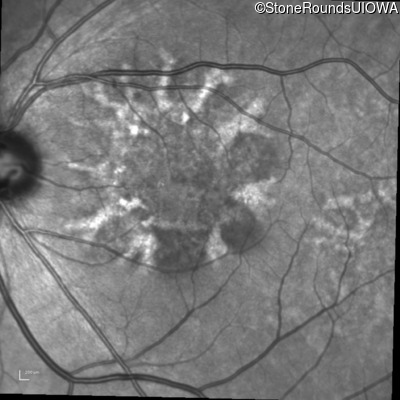

Blue Autofluorescence - Right - 20/25

Exemplar